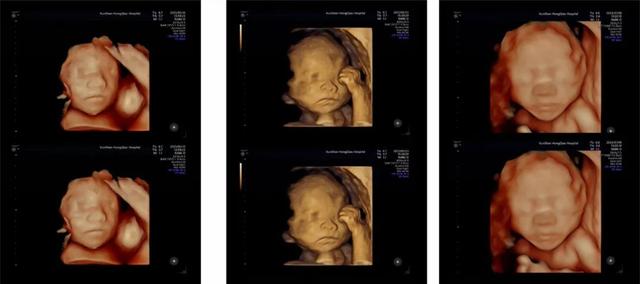

医院引进美国GE-E10高端四维彩超设备,为准父母带来清晰、动态的胎儿影像体验,让您直观感受宝贝的每一个可爱瞬间。

鲜活动态影像,清晰看见宝贝:告别传统模糊影像,实时、立体查看宝宝的五官轮廓、表情变化(如打哈欠、吮吸拳头)和灵动姿态(伸懒腰、蹬腿),打造温馨而难忘的“初见”时刻。

专业健康评估:超声团队通过清晰影像,观察胎儿生长发育、活动状态及子宫内环境,为产科医生提供有价值的影像学参考。

定格珍贵记忆:家人可共同见证宝宝实时动态,留存这份独特温馨的生命礼物。